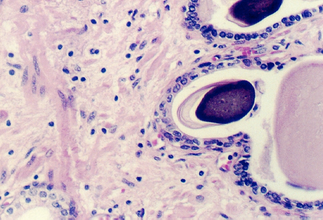

The lumen of this gland is thrown into many folds that appear to branch. This creates a labyrinth of channels, tubes, and pockets into which the secretory product flows. The epithelium shown in the photos below may be simple columnar with patches of pseudostratified epithelium. The appearance of the epithelium is variable and dependent on age and the level of androgen production. One can see some lipochrome pigment in the epithelium, which is present in elderly males. Look at the wall of the gland and again, there are numerous bundles of smooth muscle.

What does the seminal vesicle contribute to the semen?